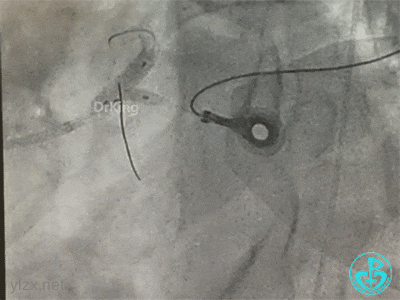

左主干分叉病变采取Crush双支架术式,回旋支开口植入支架,前降支开口球囊挤压后左主干到前降支植入支架(Crush双支架术式)。

导丝准备穿支架网眼Rewire回旋支时患者血压继续下降。去甲肾上腺素微量泵剂量逐渐增大至25ml/h,立即置入IABP,血压回升后再继续操作。

导丝Rewire回旋支,非顺应性球囊分别后扩张前降支和回旋支支架,对吻扩张。

患者术中血压偏低,一度出现烦躁。及时IABP置入是手术能顺利完成的保障。术前的准备很全面,造影结果如下。